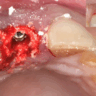

Initial CBCT images show the estimated ridge height as 1-2 mm below the sinus. The B.Y.2 diamond milling bur breaks through the sinus floor. Following the Augma Lift™ technique protocol, membrane elevation and augmentation are performed. Radiography shows implant placement 4 months post-op in newly formed bone.